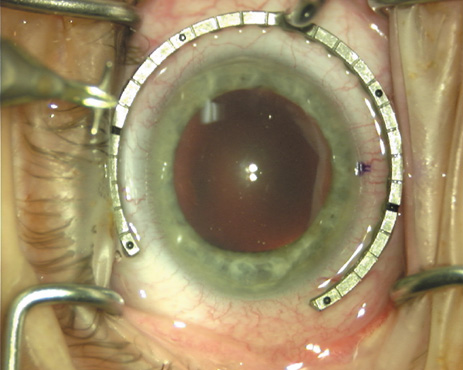

ways. Our preferred method makes use of a modified Fine-Thornton fixation

ring (Nichamin Fixation Ring and Gauge; Mastel Precision, Storz, Rhein

Medical). This instrument serves to fixate and position

the globe in order to optimize incision placement, as well as to delineate

the extent of arc to be incised. One visually extrapolates from

the limbus to marks on the surface of the ring. Each incremental mark

is 10 degrees apart, and bold hash marks (180 degrees) opposite

to each other serve to align and center the incision over the steep

meridian. This approach obviates the need to ink and physically mark

the cornea. If one desires, particularly when first gaining experience

with LRIs, a two-cut RK marker may be used to place ink marks upon the

cornea to show the exact extent of arc that is to be incised, in conjunction

with the fixation ring/gauge (Fig. 4). Alternatively, various press-on markers are available, such as

markers, rings, and blades for performing LRIs.  Fig. 4. The Nichamin Fixation Ring and Gauge serves to both fixate the globe and

delineate the extent of arc to be incised; a two-cut radial marker may

be used to mark the extent of arc to be incised, and the Mastel Nichamin

Force AK Diamond Blade with preset depth of 600 microns. Fig. 4. The Nichamin Fixation Ring and Gauge serves to both fixate the globe and

delineate the extent of arc to be incised; a two-cut radial marker may

be used to mark the extent of arc to be incised, and the Mastel Nichamin

Force AK Diamond Blade with preset depth of 600 microns.